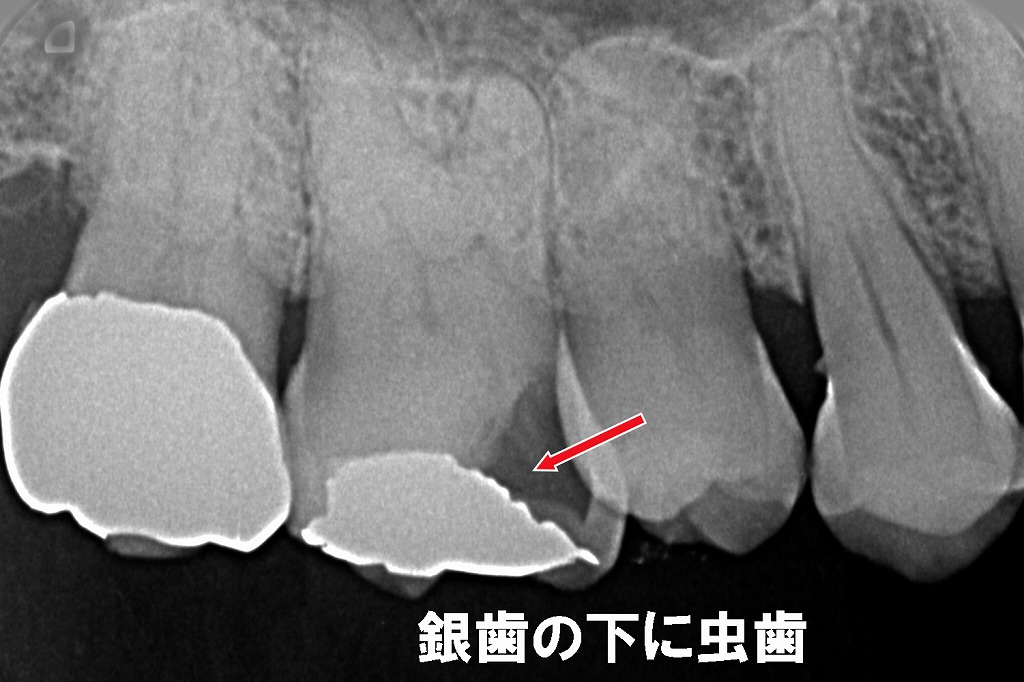

治療した歯の下で再び虫歯が進行することを「二次カリエス」といいます。

銀歯は経年劣化で劣化や浮きが生じやすく、その隙間から虫歯菌が入り込むと気づかないうちに進行してしまうことがあります。レントゲンや精密検査での確認が必要です。

上顎6番の銀歯の内部で神経近くまで虫歯(二次カリエス)が進行している様子を示すレントゲン画像です。

銀歯と歯との間にすき間が生じると、その下で虫歯が広がりやすく、治療後に「しみる」「痛む」といった症状の原因になります。虫歯が神経付近まで達すると、再治療や根管治療が必要になることがあります。